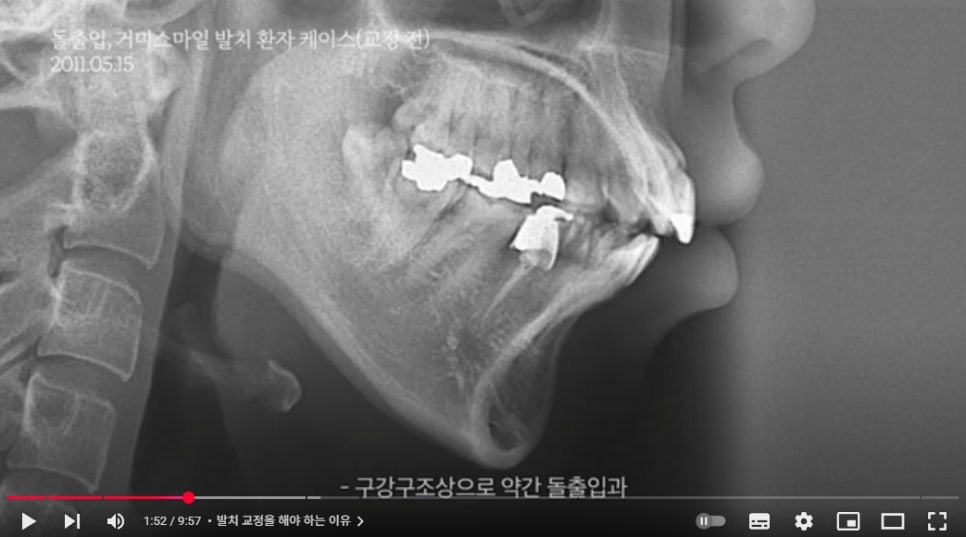

(1) 치아가 돌출된 경우

치아가 돌출된 경우, 심한 덧니가 있는 경우는

치아 발치를 진행하여 치아가 이동할 공간을 확보해야

치아를 좌/우/앞/뒤로 충분히 이동하고

돌출과 치아배열을 개선할 수 있기 때문에

발치교정이 권장됩니다.

돌출입 교정을 진행한다면

2~3mm 정도의 돌출은 발치 없이,

악궁 확장과 어금니의 후방 이동을 통해서

개선할 수 있습니다.